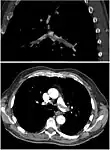

CT pulmonary angiography

CT pulmonary angiography (CTPA) is a pulmonary angiogram obtained using computed tomography (CT) with radiocontrast rather than right heart catheterization. Its advantages are that it is accurate, it is non-invasive, it is more often available, and it may identify other lung disorders in case there is no pulmonary embolism. The accuracy and non-invasive nature of CTPA also make it advantageous for people who are pregnant.[61]

On CT scan, pulmonary emboli can be classified according to the level along the arterial tree.

Segmental and subsegmental pulmonary emboli on both sides- CT pulmonary angiography showing a "saddle embolus" at the bifurcation of the main pulmonary artery and thrombus burden in the lobar arteries on both sides